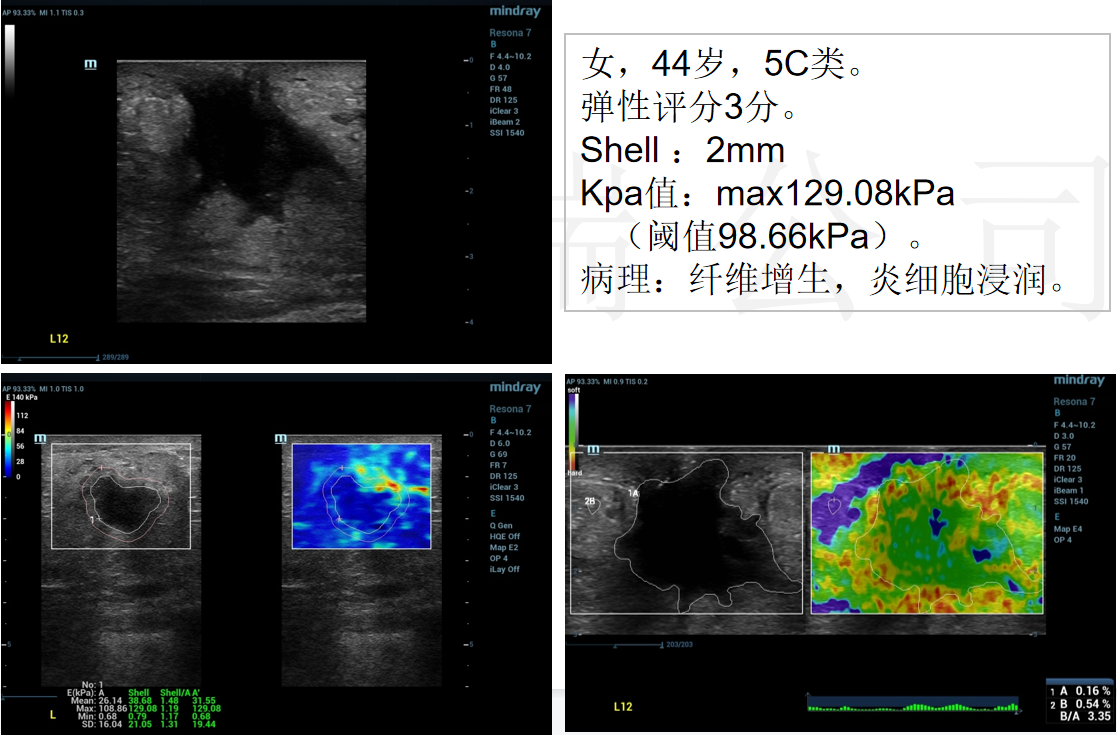

3、乳腺纤维增生,炎性细胞浸润(病例来源四川省人民医院)

6、乳腺复杂硬化性腺病(贵州医科大学附属医院):女,44岁,4c类。